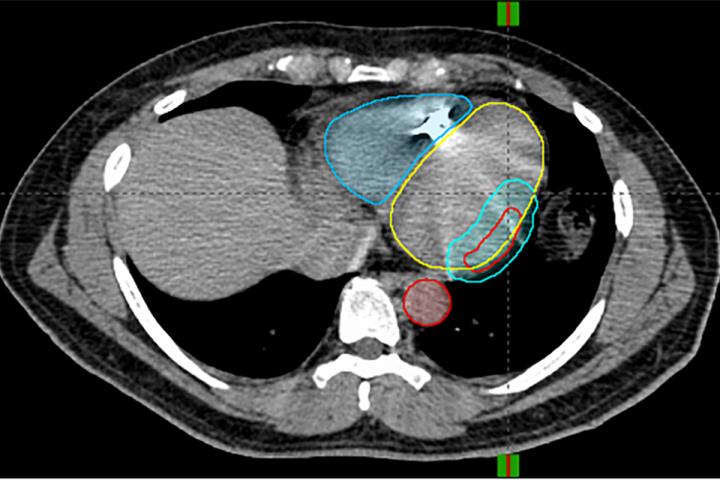

"A traditional catheter ablation procedure can take six hours or more and requires general anesthesia," Cuculich said. "This new process is entirely noninvasive. We take pictures of the heart with various imaging methods -- MRI, CT, PET scans. But the unique piece is the noninvasive electrical mapping called electrocardiographic imaging. This allows us to pinpoint where the arrhythmias are coming from. When we overlay the scar mapping with the electrical mapping, we get a beautiful model of heart function that lets us see not only where the arrhythmia comes from, but where it might progress.